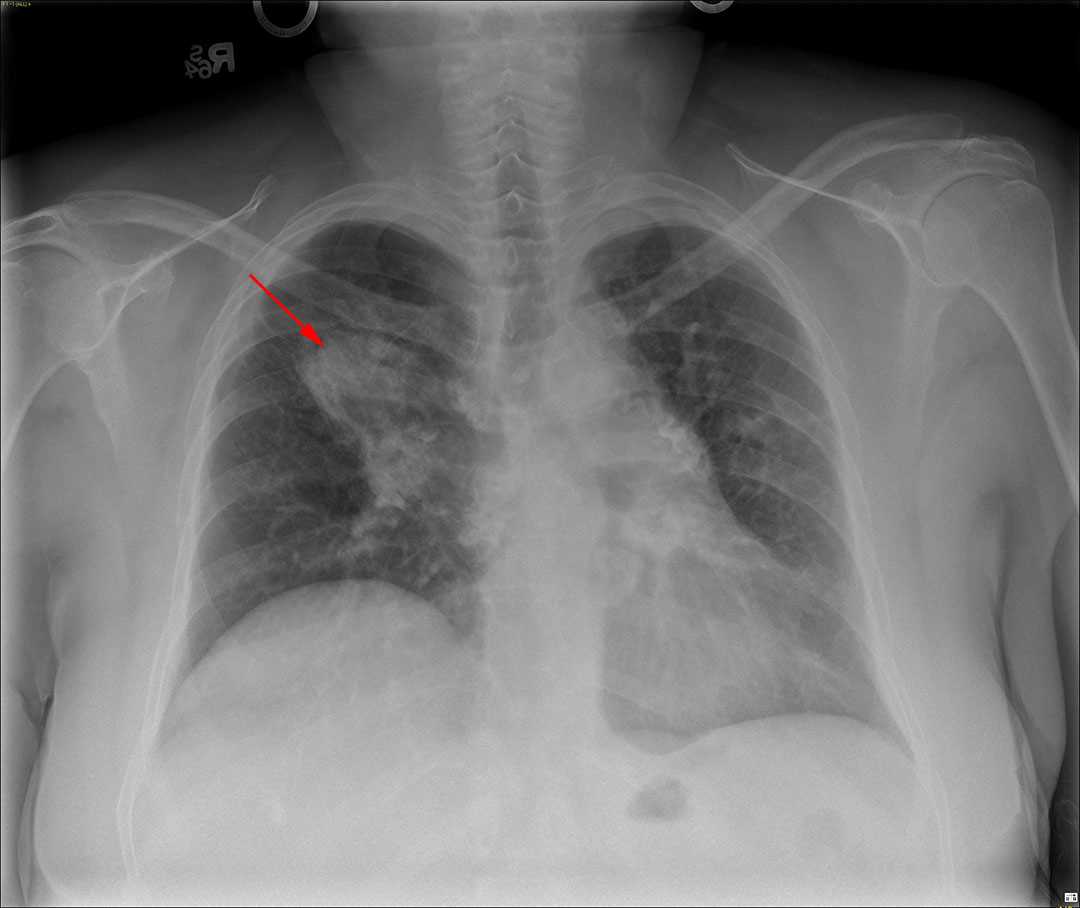

This is a patient who presented with fever as well a forearm pain and swelling. Frontal and lateral radiographs of the forearm were obtained. The frontal radiograph demonstrates abnormal cortical thickening of the radius as demonstrated by the red arrow. The green arrow demonstrates a well corticated radiolucent lesion within the medullary cavity of the distal radius. This lesion is an intramedullary bone abscess also known as a Brodies abscess. The thickened cortex of the radius is secondary to chronic osteomyelitis. Overall, the findings are consistent with chronic active osteomyelitis. Treatment is surgical debridement of the osseous abscess as well as long term antibiotics.